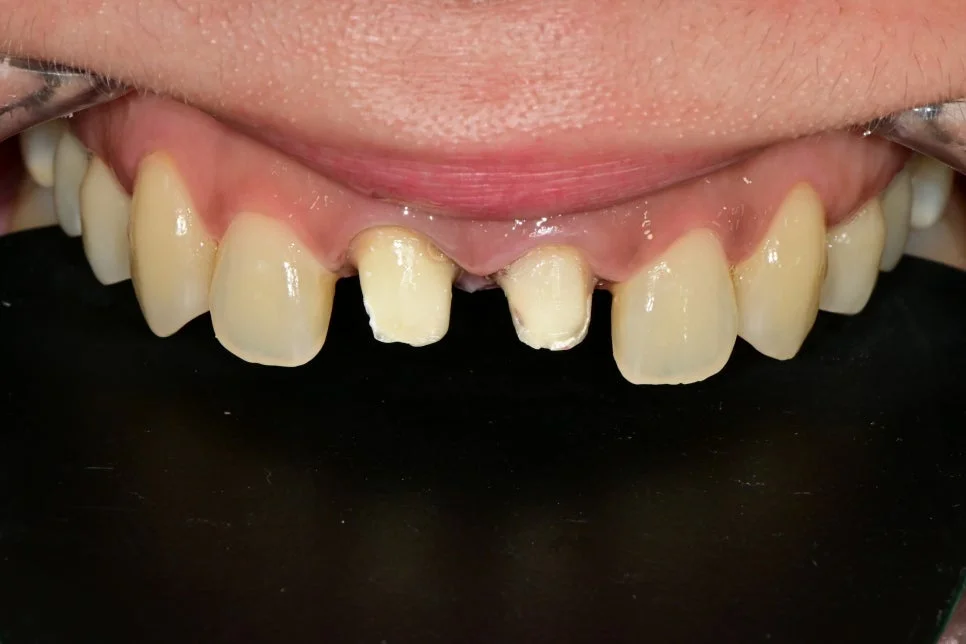

이번 포스팅에서 소개할 내용은 앞니를 신경치료 후 크라운을 씌웠는데, 점점 잇몸이 검게 변한 경우인데요.

이 환자분은 “웃을 때마다 검게 변한 잇몸과 앞니가 싫다”라며 내원하셨고, 소문난 미백 맛집 치과답게 아름답게 심미적인 부분을 회복시켜드린 사례이니 실제 예시를 통해 보실까요!

앞니 크라운 잇몸 변색으로 검게 그을린 듯한 잇몸이 관찰되었는데요.

크라운 제거 후 모습입니다.

제거하기 전 예상보다 훨씬 더 크라운 잇몸 변색이 심한 상태였는데요. 이렇기에 조기에 치료하는 게 매우 중요합니다.

안쪽을 확인해봐도 오염이 심하게 진행된 상태가 보여집니다.